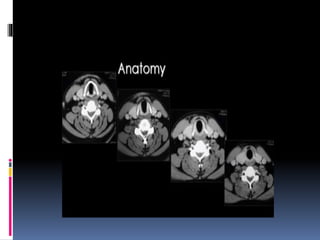

Imaging of the ear

Superior surface of petrous bone

Medial surface of petrous

bone